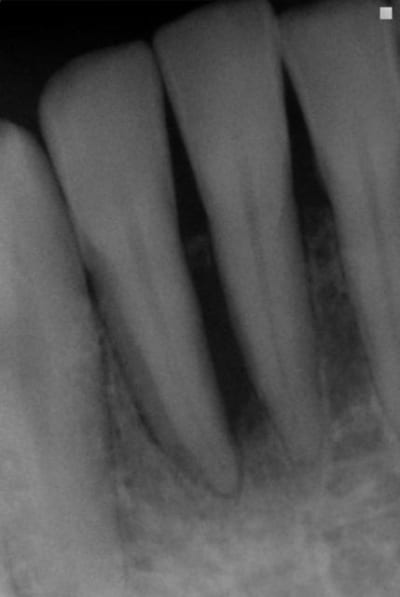

ce cas me remet en mémoire un article de charon: "le fibroblaste est- il radio opaque?"

pca patient 45 ans

flore incompatible, batonnet et spirochètes

abcès vestibulaire 42

birodogyl et séances de lithotritie+ soins locaux désinfection de juin à novembre avec irrigation bétadine

zône non sondées jusqu'à guérison radio

il y a encore un an , j'aurais été très dubitatif sur l'avenir de cette dent. Maintenant, j'y regarderai à deux fois avant de porter un jugement hatif........car les fibroblastes ne sont pas radio opaques!

J'étais plus intervenu depuis longtemps parcequ'on m'avait dans les hautes sphères d'eugénol,demandé de me calmer,mais je peux pas laisser passer ça.On est dans un cas typique de guérison à la Sainte Carole, priez pour nous.La radio de départ elle est pourrie de chez pourrie.Comment on peut faire un diagnostic dans ces conditions?Comment on peut affirmer qu'il y a eu guérison, s'il n'y avait pas de lésion au départ.C'est absolument n'importe quoi.Il suffit de passer ces deux images à photoshop pour se rendre compte que les niveaux ne correspondent pas,et que sur la première image on est surexposé,ce qui brûle obligatoirement certaines zones de l'image,et que sur la deuxième on est sous exposé.Dans ces conditions,c'est ni six mois,ni trois,ni un jour,c'est en une seconde que je vous obtiens autant de guérisons miraculeuses que vous voulez.Y a vraiment personne qui réfléchit ici avec sa tête au lieu de s'extasier sur rien?pierres,va faire un stage de prise de radio avant de penser que tu es devenu un parodontiste émerite.

Meme si tu n y met pas les formes ta raison, sur la premiere radio on voit un defaut oseux evident masi on remarque aussi le sommet du septum interdentaire ... La preuve que la radio a été sur exposée

la différence d'exposition entre les deux clichés est évidente aussi, et c'est un défaut de la présentation.

Ceci dit , cela rend intéressant à postériori l'usage des réglages contrastes pour visualiser l'os à perdre ou à regagner. Le numérique nous le permet. La question étant y a t il encore une trame ou plus rien.

en fait sur ce cas, ce qui m'a inquiété c'est ce que je ne voyais plus sur la radio

alors que ce qui aurait dû me rassurer c'est ce qu'on y voyait encore